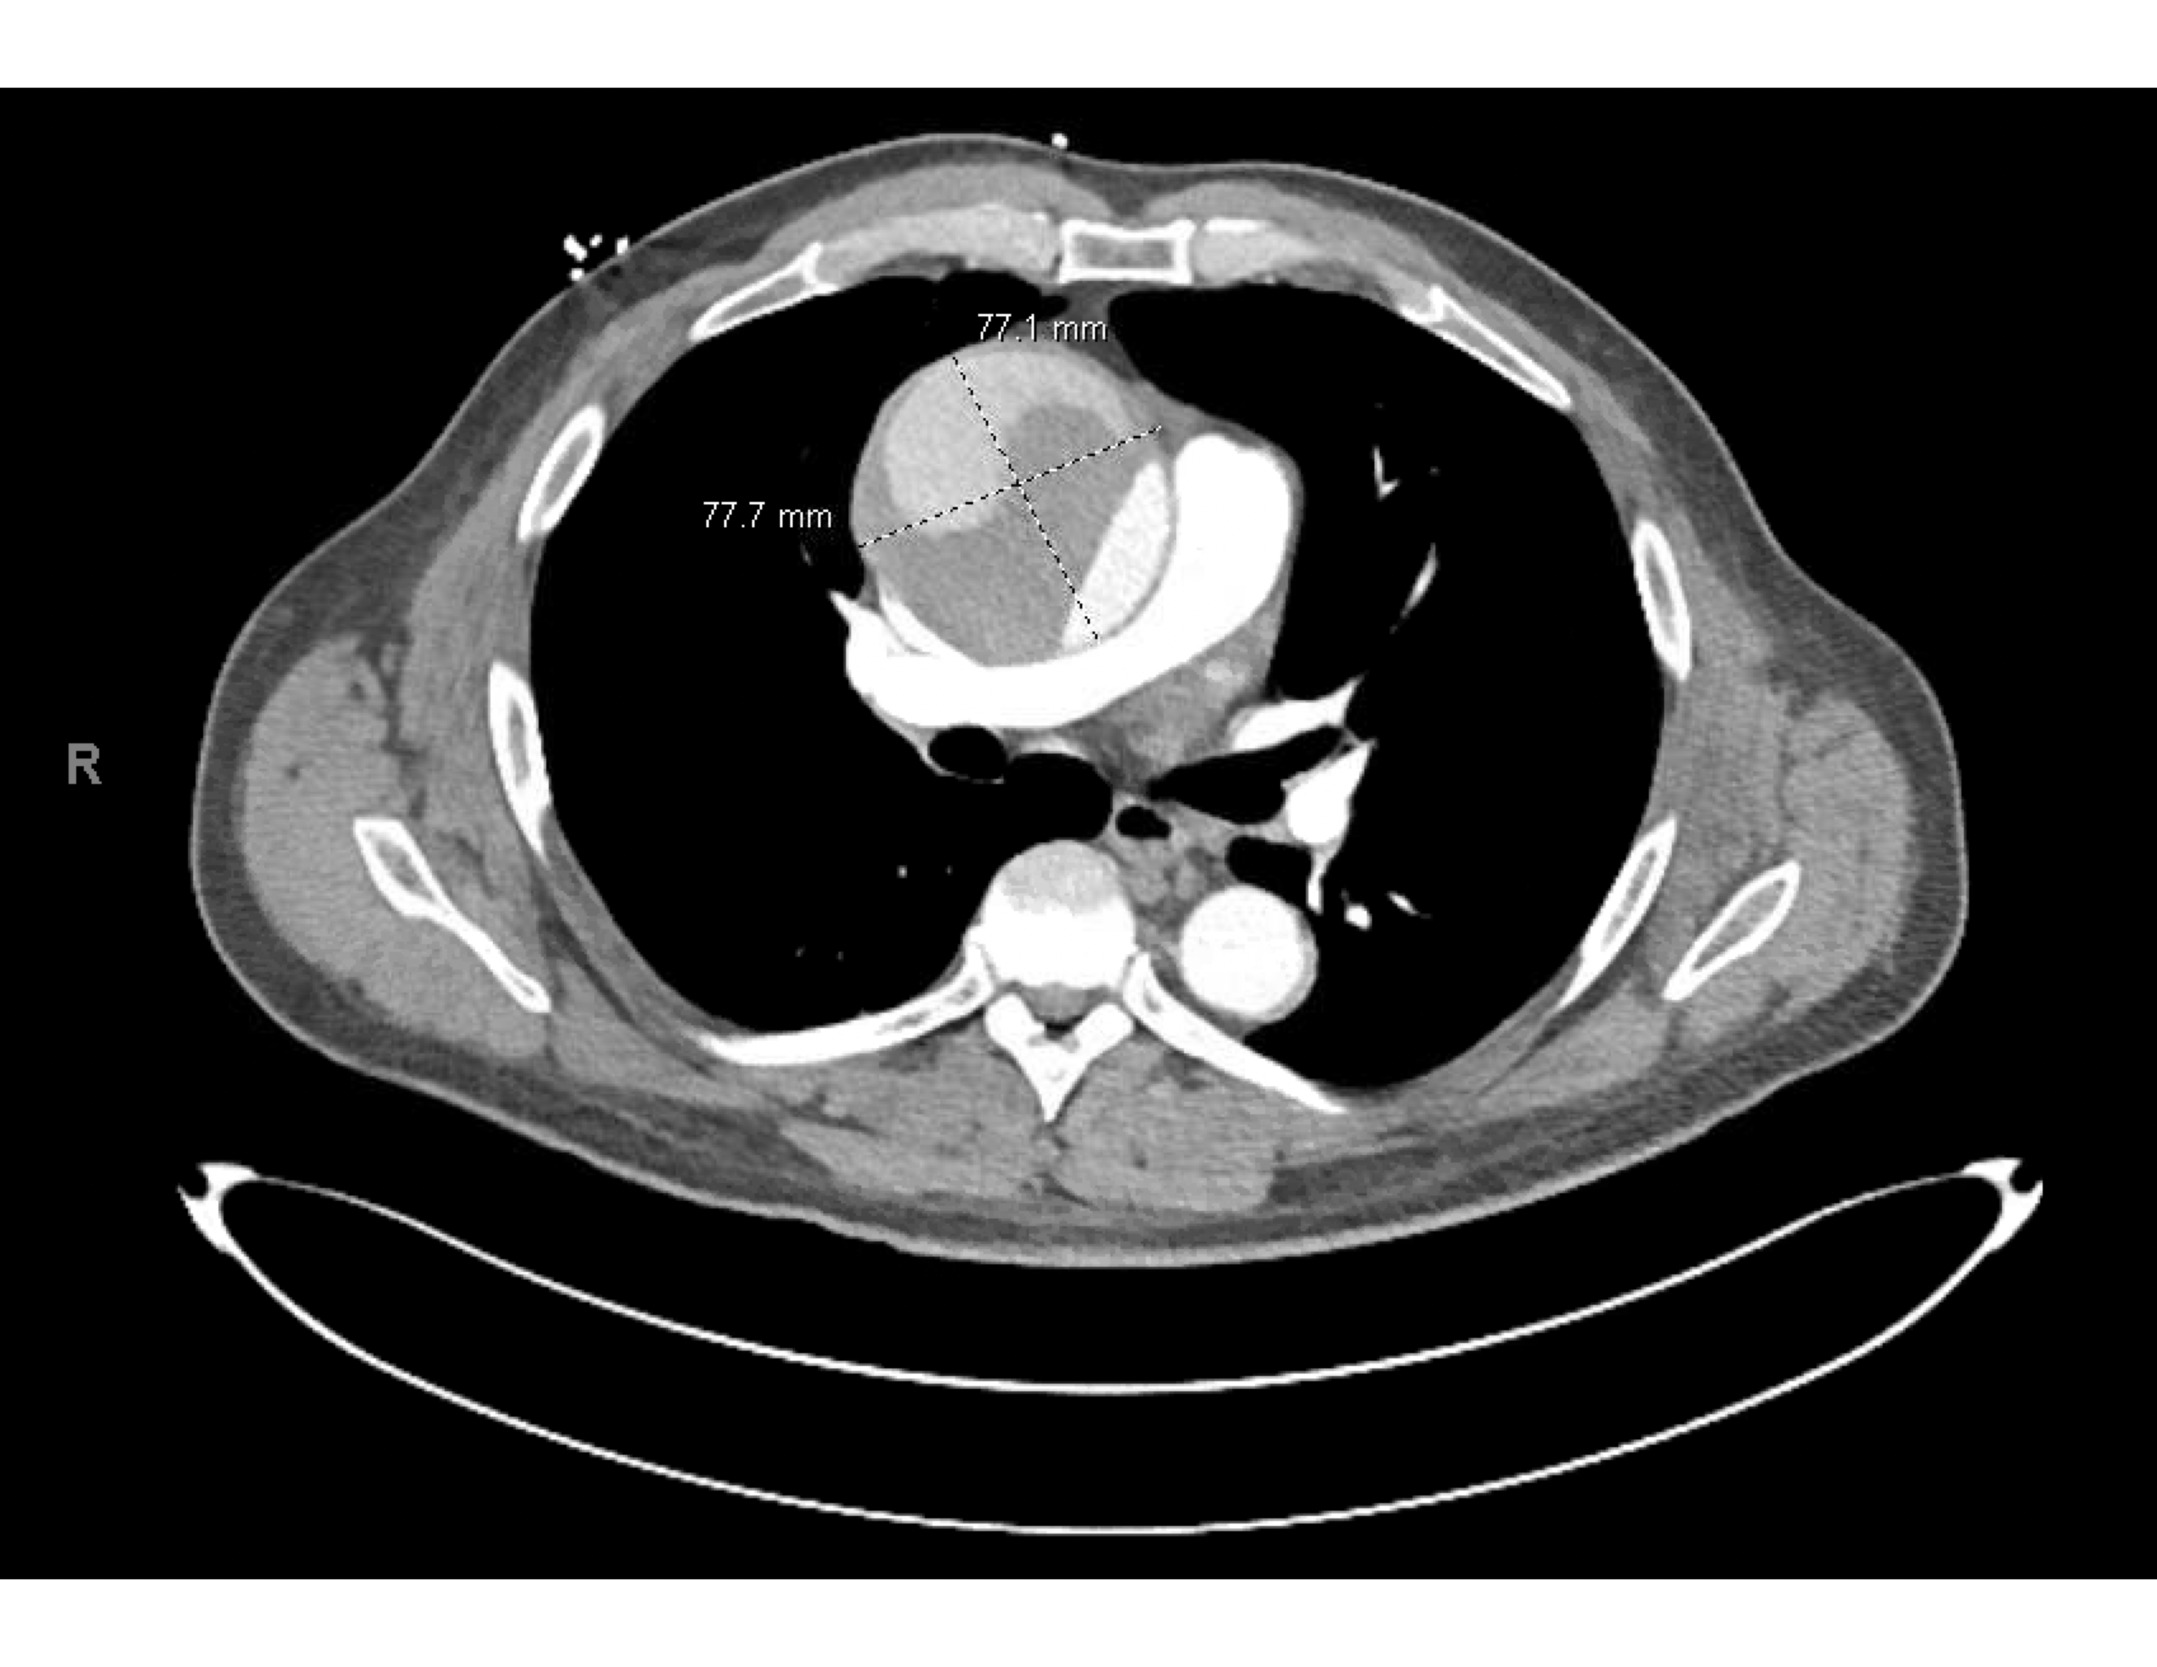

However, upon further careful medical history taking, the patient also reported chest pain that started that morning. He stated that the pain was located over the left side of his chest, felt sharp, was intermittent, but not worsened with exertion. He denied any recent upper respiratory infection, trauma to the chest, history of drug use, or previous history of chest pain.6 Although his blood pressure and heart rate were mildly elevated, his cardiac examination was normal, and he had good pulses in all of his extremities. We ordered tests to assess for potential acute coronary syndrome including electrocardiograms (ECG), high sensitivity troponins, and chest radiography. The ECG (Figure 2) showed sinus tachycardia at about 102 beats per minute, poor R wave progression across the precordial leads suggestive in this case of previous anteroseptal injury, and left ventricular hypertrophy per the modified Cornell criteria, but no ST segment elevations concerning for acute cardiac ischemia. The high-sensitivity troponin was very minimally elevated to 0.07 and downtrended to 0.06 three hours later. All other labs were grossly unremarkable besides mildly elevated liver function tests. The portable chest radiograph, however, showed a modestly widened superior mediastinum, as pictured in Figure 3. We quickly proceeded with a bedside ultrasound which showed a large ascending aortic aneurysm (Figure 4) with an associated proximal aortic dissection. In Figure 5, a dissection flap can be clearly visualized. After consulting with cardiothoracic surgery while starting the patient on an esmolol drip for blood pressure and impulse control, we obtained a CT angiogram of the chest which showed a 7.7 cm dissecting aneurysm involving the ascending aorta and proximal aortic arch with a large, partially thrombosed false lumen and extension into the proximal innominate artery (Figure 6). The radiologist also noted there was marked compression of the superior vena cava (SVC) due to the large aneurysm of the ascending aorta. The patient later required a nicardipine drip after high-dose esmolol failed to optimally control his hyperdynamic state.